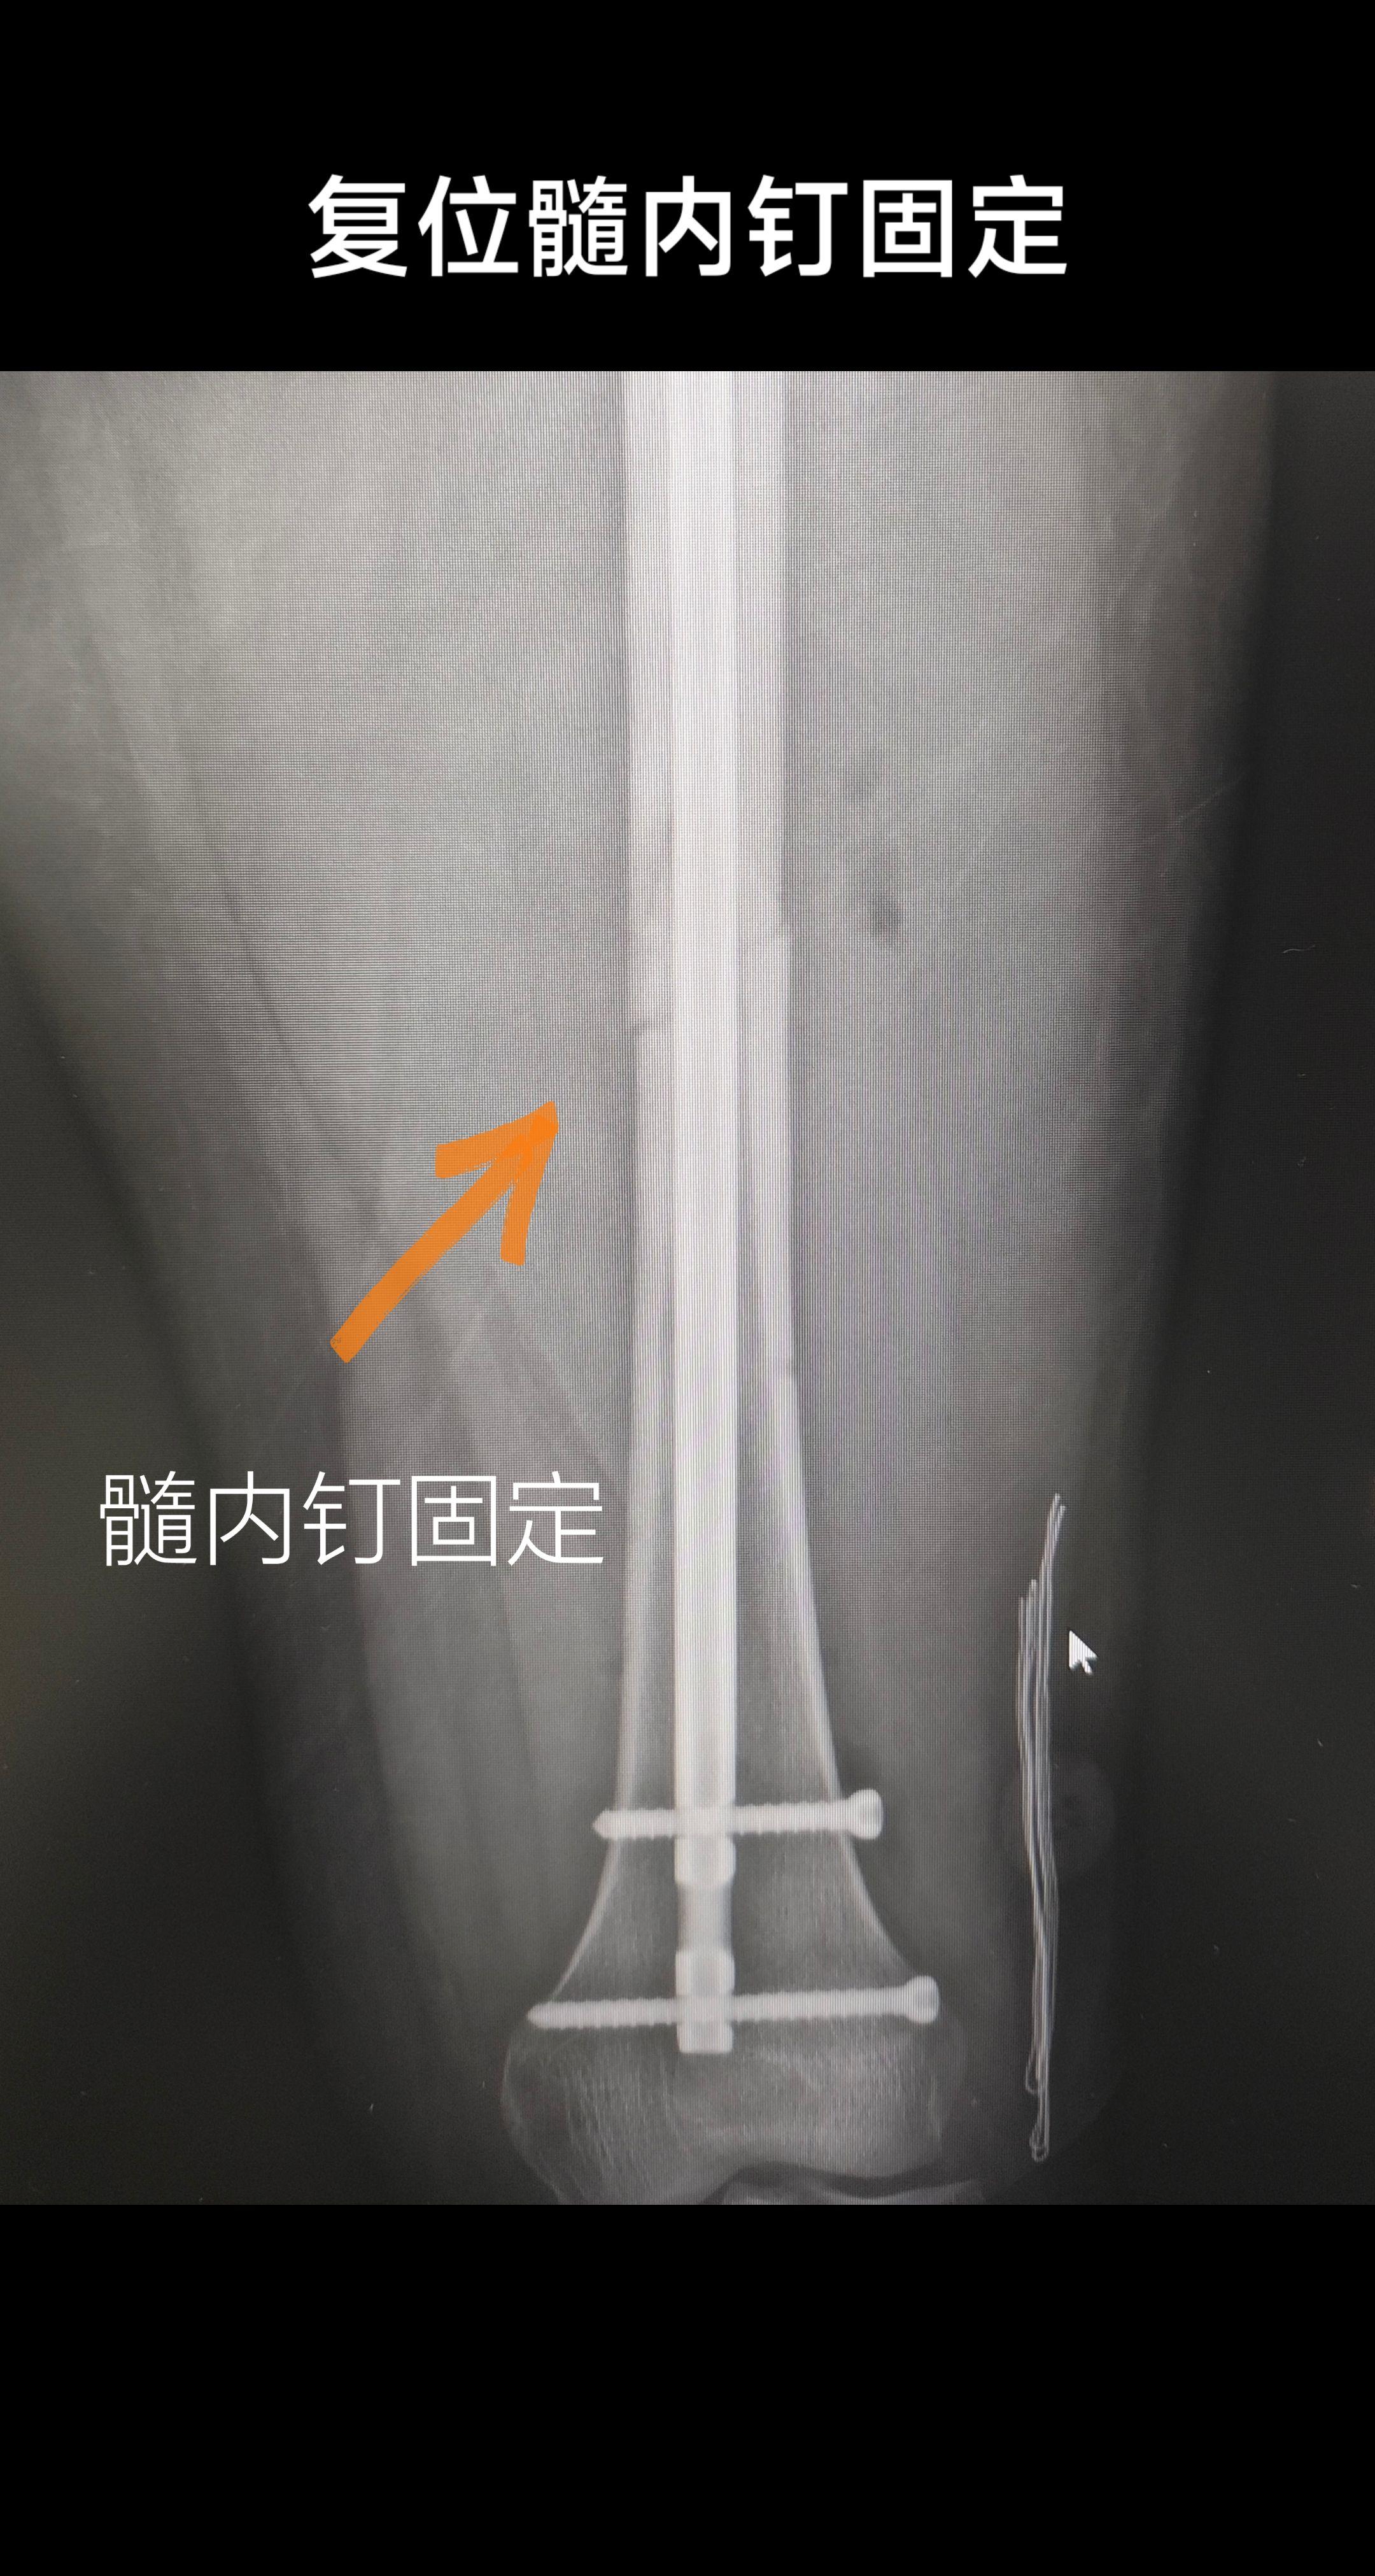

股骨骨折。